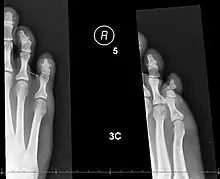

X-rays of fractures of the proximal (left) and distal (right) phalanges in the little toe.

X-ray shows a small portion broken off the corner of the distal bone, and a [more longitudinal fracture in the bone in the middle of the toe?},